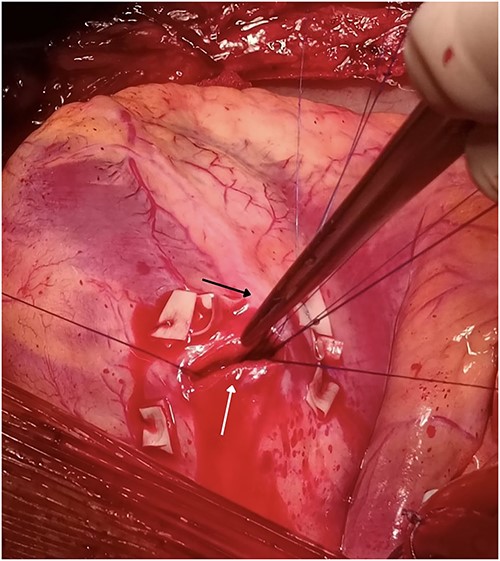

Our team performed urgent sternotomy, pericardiotomy and evacuation of hemopericardium, and only then was the full extent of the injury verified – a penetrating wound to the LV which measured ~2 cm and transected the second diagonal branch of LAD (Fig. 2). The knife missed the LAD by ~2 mm.

Penetrating wound to the LV measuring 2 cm (white arrow) missing the LAD (black arrow) by 2 mm but transecting the second diagonal branch of the LAD.

The heart was then put in cardioplegic arrest and the procedure was carried out with the help of a cardiopulmonary bypass machine. The wound was closed using seven interrupted monofilament sutures with pledgets made from a porcine pericardial patch.